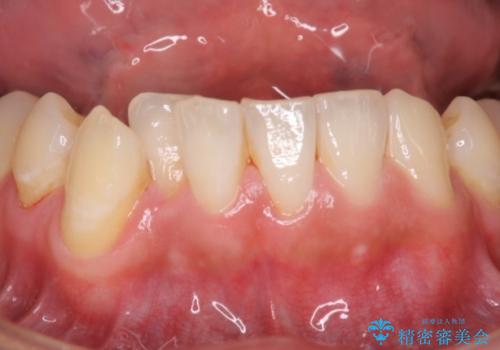

- 結婚式を控えており、それまでに歯を白くしたいということで来院されました。

歯医者に来院するのが久しぶりの様で歯の表面に汚れが付着しているとホワイトニング薬剤の効果が薄れるため、術前のクリーニングをおすすめしその後オフィスホワイトニングエクセレントコースを行いました。

全体的にトーンアップしました。オフィスホワイトニングはホームホワイトニングに比べ1度で白くなりやすいため、直近の予定を控えている方にお勧めしております。